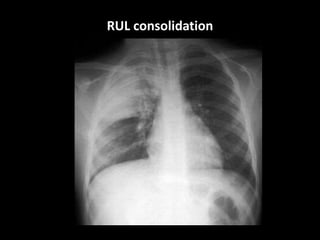

RUL consolidation